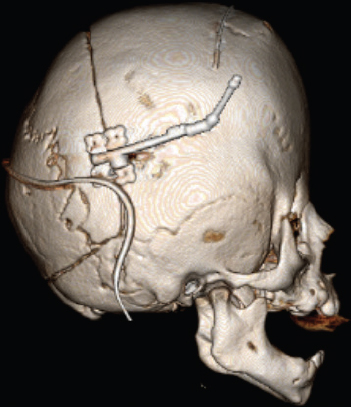

CHAPTER Normal skull growth and potential neurologic function may be affected by the presence of continued pressure in any one area of the cranium or by the presence of one or more pathologically fused cranial sutures. Posterior deformational plagiocephaly, most often secondary to a supine sleeping position, will generally resolve with positional changes, physiotherapy, or helmet therapy and is only rarely a surgical condition. The presence of a pathologically fused suture will produce deformity of the skull and is frequently an indication for operative release. The fused sutures determine the phenotype of the craniofacial deformity. According to Virchow’s Law, bone growth can no longer occur across (perpendicular to) the affected suture and therefore only occurs along it (parallel)1 (Fig. 41.1). Craniosynostosis can be classified into simple (single suture) versus complex (multiple sutures) and nonsyndromic versus syndromic subtypes. Assessment of an infant with an abnormal head shape includes a detailed medical history and physical examination to rule out a positional cause and identify any complicating sequelae. The medical history should identify any history of skull irregularities, associated syndromes, family history of calvarial deformities, and symptoms of intracranial hypertension (headache or vomiting, developmental changes, irritability, or oculomotor paresis). Often, parents note an abnormal head shape at the time of delivery or one that becomes more apparent later in infancy. Patients with irritability, feeding difficulties, failure to thrive, headache, developmental delays, visual changes, marked turricephaly, supraorbital recession, bulging or “tight” fontanels, abnormal distended scalp veins, or a lack of circumferential skull growth may have an increase in intracranial pressure. For patients with head shape abnormalities, a careful physical examination should be able to identify the cause. Positional deformation presents with a classic parallelogram appearance when looking from above. Skull deformation caused by premature fusion produces characteristic findings, including asymmetry (supraorbital retrusion, towering or turricephaly, frontal or occipital bossing), inability to palpate the anterior fontanelle (which normally remains open until 12 to 18 months of age), perisutural ridging, and signs of intracranial hypertension (papilledema). Studies have shown that the presence of intracranial hypertension is dependent on the number of affected sutures, ranging from approximately 14% for single-suture synostosis to approximately 47% in multisuture synostosis.2,3 Suture release in craniosynostosis is often offered to correct the craniofacial deformity and to address potential increased intracranial pressure that in some patients has resulted in blindness and developmental delay. Fig. 41.1 Virchow’s law: Bone growth can no longer occur across (perpendicular to) a fused suture and therefore only occurs along it (parallel). The specific calvarial shape can indicate which sutures are involved. Children with sagittal synostosis present with a narrow, elongated skull (dolichocephaly describes long-headedness; scaphocephaly describes a boat-shaped head). Depending on the region of greatest fusion of the sagittal suture, the child may manifest frontal or occipital bossing or a combination of both. Some children will also demonstrate a “towering” skull, also known as turricephaly. Metopic synostosis is marked by a variable degree of phenotypic severity, ranging from mild ridging to the formation of a triangular head (trigonocephaly) or prominent “keel” forehead with or without hypotelorism. Although an endocranial ridge is not commonly seen in patients with metopic synostosis, an endocranial notch can be observed on axial CT images and is virtually diagnostic of pathologic suture fusion. Patients with unicoronal synostosis present with anterior plagiocephaly, whereas those with bilateral coronal involvement demonstrate brachycephaly. Phenotypic features of anterior plagiocephaly include ipsilateral perisutural ridging, forehead flattening, and orbital recession, coupled with contralateral compensatory frontal bossing. Facial deformities are also common, including nasal root displacement toward the ipsilateral side, anterior displacement of the ipsilateral ear, and chin deviation toward the contralateral side, resulting in a classic C-shaped craniofacial deformity—concave contralateral to the fused suture. Children with lambdoid synostosis characteristically have a trapezoid-shaped head (seen from the vertex view) in association with posterior displacement of the ipsilateral ear, contralateral occipital bossing, ipsilateral mastoid bossing, and ridging of the affected lambdoid suture. In contrast, posterior deformational plagiocephaly is marked by a parallelogram-shaped head when viewed from the vertex, anterior displacement of the ipsilateral ear, ipsilateral frontal bossing in the absence of palpable lambdoid suture ridge, and no mastoid bossing as is seen with lambdoid suture fusion (Fig. 41.2). Posterior plagiocephaly caused by lambdoid suture synostosis is rare; the majority of posterior plagiocephaly is secondary to positional molding. Understanding the phenotypic differences between lambdoid synostosis and posterior deformational plagiocephaly is critical for making the appropriate diagnosis and designing the proper course of treatment. Head circumferences, cranial indices, and anthropometric measurements should also be noted. Imaging studies may be necessary to confirm the diagnosis and rule out any associated intracranial abnormalities. For younger patients, ultrasonography has been used as a screening tool to visualize the sutures through the open fontanelles. Although not as sensitive as computed tomography (CT), it avoids the risk of radiation exposure. CT remains the most sensitive modality to assess bony sutural fusion and may suggest elevated intracranial pressure, as noted by areas of erosion of the inner calvarial table (“copper-beaten” appearance) (Fig. 41.3). Pathognomonic for unicoronal synostosis, elevation of the ipsilateral orbit can be seen secondary to superior displacement of the greater wing of the sphenoid, also known as the “harlequin” deformity. Modern CT protocols attempt to minimize the radiation dose to the infant.4 Both CT and magnetic resonance imaging (MRI) are helpful in evaluating the underlying brain for structural or functional abnormalities, including hydrocephalus, holoprosencephaly, cortical dysplasias, and Chiari malformations. The latter are structural defects in the part of the brain that controls balance (cerebellum). Without sufficient space, the cerebellum and parts of the brain stem may sit too low, causing pressure and blocking the flow of cerebrospinal fluid. This is important to identify preoperatively, because intraoperative maneuvers may worsen the condition. Summary Box Common Complications in Synostosis Correction Intraoperative • Bleeding • Venous air embolism • Ocular injury and vision loss • Dural and brain injury, cerebrospinal fluid leak • Death Postoperative • Infection • Growing skull defects • Persistent calvarial defect • Hardware-related complication • Restenosis, relapse, growth restriction, and recurrence of deformity Surgical intervention is indicated in craniosynostosis to correct the craniofacial deformity and potentially treat or prevent functional disabilities believed to be secondary to intracranial hypertension (blindness, developmental de lay, psychosocial dysfunction). Patients with multisutural synostoses present with increased severity of physical and neurologic symptoms; therefore surgical intervention is even more important. The optimal surgical age has been debated, because the techniques of surgery are variable. Although the literature is inconclusive regarding the appropriate timing for correction of craniosynostosis, most craniofacial surgeons operate within the first year of age, taking into consideration the number and pattern of suture fusion, evidence of intracranial hypertension, and the surgical technique chosen. Minimally invasive techniques, which rely on less extensive craniotomies and external postoperative molding, are generally performed at an earlier age than are traditional open techniques. The technical portions of the procedures are complicated and have multiple risks. Avoidance of these risks is important to produce improved results. This begins with carefully evaluating potential patients preoperatively and optimizing their physical condition before surgery. In preparation for surgery, measures to ensure stable blood volumes should be undertaken. These include obtaining a baseline hemoglobin, blood type and crossmatch, and potential directed blood donation from a matched family member. Some surgeons use preoperative erythropoietin to minimize the need for transfusion.5 Surgery is performed under general anesthesia, which should be provided by a fellowship-trained pediatric anesthesiologist. Patients should be monitored postoperatively in an intensive care unit under the direction of pediatric critical care–trained physicians. A broad range of surgical options has been proposed for the surgical treatment of craniosynostosis. The goal of each is to remove the affected suture and either immediately remodel the remaining calvarial vault or provide postoperative guidance (distractors, springs, helmets) to allow this to occur. For most types of craniosynostosis repairs, patients are placed in the supine position to facilitate exposure. However, if the posterior vault is being addressed, as in a lambdoidal synostosis or some sagittal synostoses, the patient may be placed in the prone or sphinx position . In the prone position, care must be taken to ensure proper positioning with adequate protection of the eyes. Injury to the globe is devastating and should be a “never event.” Before the procedure begins, lubrication should be placed over the corneas; some surgeons approximate the eyelids with either adhesive tapes or formal tarsorrhaphy sutures that can be removed at the conclusion of the procedure. If the patient must be in the prone position, the face can be supported with a foam pillow or horseshoe headrest, with the eyes uncompressed within the opening of the support. Venous air embolism (VAE) is the introduction of air or gas from the operative field into either the arterial or venous vasculature and is a potentially fatal complication of neurosurgical procedures.6 Previous studies have suggested that the rate of VAE may be as high as 80% during such procedures. This may be lower for endoscopic techniques.7 Some believe that real-time monitoring, to identify the presence of a venous air embolism and allow for immediate intervention, mitigates the risk. Despite the introduction of newer diagnostic techniques, use of a precordial Doppler remains a standard modality. Although transesophageal echocardiography is the most sensitive method of detection,8,9 it is more costly and invasive. When properly placed between the third and sixth intercostal spaces along the right parasternal border, a precordial Doppler is potentially capable of identifying VAE at an air infusion rate as low as 0.015 mL/kg/min and consistently at a rate of 0.021 mL/kg/min.10,11 VAE may be graded by severity: change in Doppler tones (grade I), change in Doppler tones and decrease in end-tidal carbon dioxide (grade II), or decrease in systolic blood pressure by 20% from baseline (grade III). The calvarium is often approached via a standard “stealth” (zigzag) coronal incision, providing for adequate exposure while minimizing any postoperative scar. Perioperative antibiotics and steroids may be administered before the procedure. The incision is infiltrated with 1:200,000 epinephrine in 0.5% lidocaine to minimize bleeding along the incision site. The frontal and temporal regions are dissected in the subgaleal plane, and care is taken to preserve the periosteum on the surface of the bone, which helps minimize blood loss and may be used to stabilize the bony segments. Bleeding can occur at several points in the procedure. Incisions into the scalp can produce significant bleeding in the infant. This bleeding can be controlled with metal clips and cautery. Bleeding can also occur with elevation of the coronal flap. This is usually greater with subperiosteal dissection rather than supraperiosteal dissection. With either, punctate bleeding should be controlled with pinpoint cautery or bone wax. The latter should be used judiciously, because any wax left behind can serve as a nidus for infection. To “turn down” or reflect the coronal flap, the supraorbital vessels must be released from their attachments to the frontal bone. Sometimes, the vessels exit the bone through a notch; in older children they exit through a foramen. If the surgeon is not careful of these vessels, unnecessary bleeding can occur. When the vessels may exit through a foramen, a 2-mm osteotome should be used to convert the foramen to a notch by removing the inferior portion with the bony foramen. The vessels within the underlying periorbita can then be carefully dissected away from the bone. Performing the craniectomy involves making several small access holes and joining them with a side-cutting craniotome with a protective footplate. The access holes are made with a high-speed burr. Injury may occur if the burr is used too aggressively to enter the calvarial vault. The burr is often used to traverse the outer table, diploic space, and a portion of the inner table. As the remaining bone becomes thin enough, the burr can be put aside and communication to the epidural space made with a fine curette. Once a small opening is made with the curette, a Kerrison rongeur can be used to widen the opening further. The Kerrison has a protective footplate to minimize dural injury. Once the opening is large enough, a small elevator, such as a No. 4 Penfield, can be used to dissect beneath the bone and above the dura along the proposed craniotomy path. Once the bone cuts have been made, the bone flap should be removed carefully to avoid additional trauma to the underlying dura from sharp edges. The most severe bleeding can occur if there is injury to the sagittal sinus. The sagittal sinus is most at risk when the craniotome passes across the midline. For this reason, any cuts traversing the sagittal sinus are performed last. In the event of significant bleeding, the bone flap can then be removed relatively quickly to address the blood loss. With the remaining bone cuts already performed, the bone flap can be removed relatively quickly and any bleeding controlled. Injury to the sagittal sinus more posterior in the skull is more worrisome. The earliest approaches to treating craniosynostosis included simple suturectomy, allowing the brain to direct skull growth through the remaining open sutures. Inadequate correction prompted more extensive procedures of calvarial remodeling, and these have yielded improved results. These current techniques include wide scalp dissection, more remote calvarial osteotomies, and skull remodeling that is individually tailored to each cranial vault deformity.12 For sagittal synostosis, the surgical approaches range from minimal removal of the involved suture (usually combined with postoperative use of springs, distractors, or helmets) to extensive total calvarectomy and reconfiguration. Simple synostectomy, or simple strip craniectomy, when combined with postoperative springs, distractors, or helmet therapy, can be safe and well tolerated, providing adequate cosmetic results in select patients with mild deformities. Disadvantages include its lack of specifically addressing the severe compensatory changes in skull shape that result from the fused suture. It also leaves a large unprotected area over the vertex of the skull, an area with a high rate of restenosis and renewed growth restriction. The midvault “expanded strip craniectomy” provides a more immediate reconstruction of skull contour by shortening the anteroposterior dimension, expanding the biparietal dimension, and partially addressing the frontal and occipital prominences. The “Pi reconstruction,” a version of a midvault expanded strip craniectomy, is used for older infants (6 to 12 months of age) with scaphocephaly caused by sagittal synostosis (Fig. 41.4). Bone is removed lateral to the sagittal suture over the lateral parietal areas and molded, leaving two bony defects in the design of the Greek letter Pi (π). Cranial bone overlying the sagittal sinus is left intact to minimize bleeding. Axial compression is used to shorten and widen the skull, and absorbable plates are placed to hold the position. For coronal and metopic synostosis, the goal is to correct the frontal and orbital asymmetries. In the former, there is asymmetry in the shape of the orbits and forehead. In the latter, the typical deformity involves a midline ridge with retrusion of the supraorbital bar (“bandeau”) on either side of the forehead. The most common technique is fronto-orbital advancement (FOA). With an FOA, dissection continues within the orbits, freeing the periorbita off the upper half of the orbit. Caution must be taken to avoid injury to the underlying globes. To expose the roof of the orbits or anterior cranial base, a bifrontal craniotomy is marked and cut with an osteotome. Typically 1 to 2 centimeters of the superior orbital rim is left for support. The bone flap is placed aside and replaced in a more corrected position at the end of the procedure The supraorbital bar or bandeau is removed with careful osteotomies through the lateral orbit at the frontozygomatic suture, the superior orbit along the roof, and the nasion just above the nasofrontal suture. Care is taken to protect the underlying dura and brain as well as the orbital contents with adequate exposure and judicious use of retractors. This is a relatively low-risk maneuver but should similarly be performed with caution. The eyes are perhaps most at risk when cutting the orbital bandeau. Here, sufficiently wide malleable retractors should be placed between the globes and the saw blade or osteotome. The saw should not be run unless there is good protection of the underlying structures and the blade only advanced through the bone as far as needed. As the blade moves either medially or laterally, the retractors should follow to avoid inadvertent injury. The sphenoid wing is cut and the coronal sutures are opened to the level of the skull base to prevent continued growth restriction and resultant postoperative hollowing of the pterional regions. The bandeau is then reconfigured and fixed with resorbable sutures or plates and screws to maintain the newly contoured shape. Reconfiguration of the supraorbital bar might require osteotomies, both in the midline to flatten the forehead and laterally to normalize the lateral supraorbital angle. The goal is expansion on the affected side as well as recession on the contralateral side. When replaced, its lateral aspects and midline are fixed to the calvarial vault. This is performed for both unilateral and bilateral cases. To avoid relapse or a persistent deformity, overcorrecting the expansion of the affected side by 5 to 10% while also providing a convex shape at the lateral border is commonly necessary for a satisfactory reconstruction. The frontal bone flap is then attached to the supraorbital bar, taking care to match it to the previously overcorrected (5 to 10%) orbital bandeau on the affected side. For lambdoid synostosis, a variety of surgical approaches, aiming to release the affected suture(s) and normalize the posterior calvarial vault contour, have been described. Options include simple synostectomy, unilateral remodeling of the affected occipital region, and bilateral occipital reconstruction with or without the use of an occipital bandeau. Most lambdoid surgical candidates have significant parietal and frontal compensatory changes in addition to their occipital deformation; therefore they are best served by a more extended calvarectomy and remodeling. The reconstruction is similarly maintained with intervening bone grafts and resorbable hardware. Titanium was used early on but fell out of favor when it was noted that the plates translocated endocranially to the internal surface of the skull with calvarial growth. Resorbable plates made of polylactic acid provide temporary support across the osteotomy sites and dissolve within 12 to 24 months. After placement of the reconfigured supraorbital bar, the frontal bone is remodeled using the remaining portions of bone and fixed with absorbable plates or suture. Closure is performed in a routine fashion, with some surgeons placing subgaleal drains. To address concerns regarding incision length, operative blood loss, and length of stay associated with open cranio-facial procedures, minimally invasive techniques have been proposed. These techniques include endoscopic sutural release,13 spring-assisted cranioplasty14 (Fig. 41.5), and distraction osteogenesis15 (Fig. 41.6). Endoscopic release has been proposed to minimize the intraoperative risks by limiting the amount of bleeding from larger scalp incisions and bone flap elevation. The technique uses one or more small incisions, minimal dissection, and removal of the affected suture, possibly with adjunctive osteotomies into the surrounding bone. The technique does not attempt to completely correct the craniofacial deformity at the time of surgery but rather remove the offending sutures and allow remodeling during a period of postoperative brain growth, with or without external molding, or distractive force. The use of springs works in a similar fashion; the affected suture is removed and one or more internal springs are placed across the open osteotomy to guide remodeling of the skull (see Fig. 41.5). Of note, a second, smaller procedure is required to remove the springs. Similarly, distraction osteogenesis has been used to impart an internal force across the ostectomy site (see Fig. 41.6). New bone is laid down in the distracted osteotomy gap.